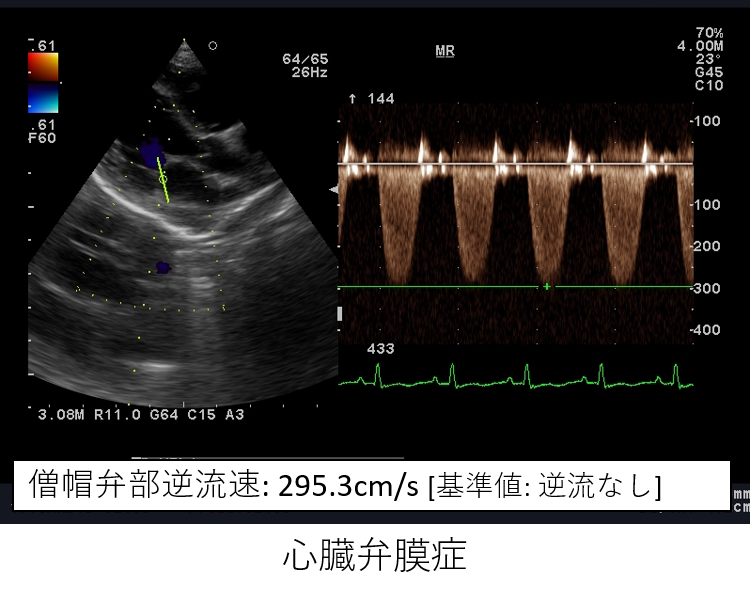

キャンパス内には、動物病院や農場、演習林、動物医科学センターなど、実際に手を動かして学べる施設が勢ぞろい。MRIやCTなどの最新医療機器を備えた附属動物病院では、臨床現場さながらの学びが可能です。